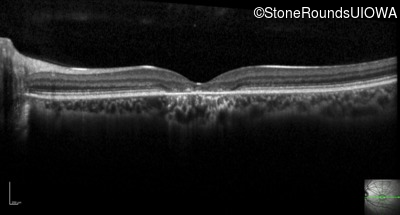

Optical Coherence Tomography - Right - 20/160

Exemplar / OCT Stack

OCT Stack